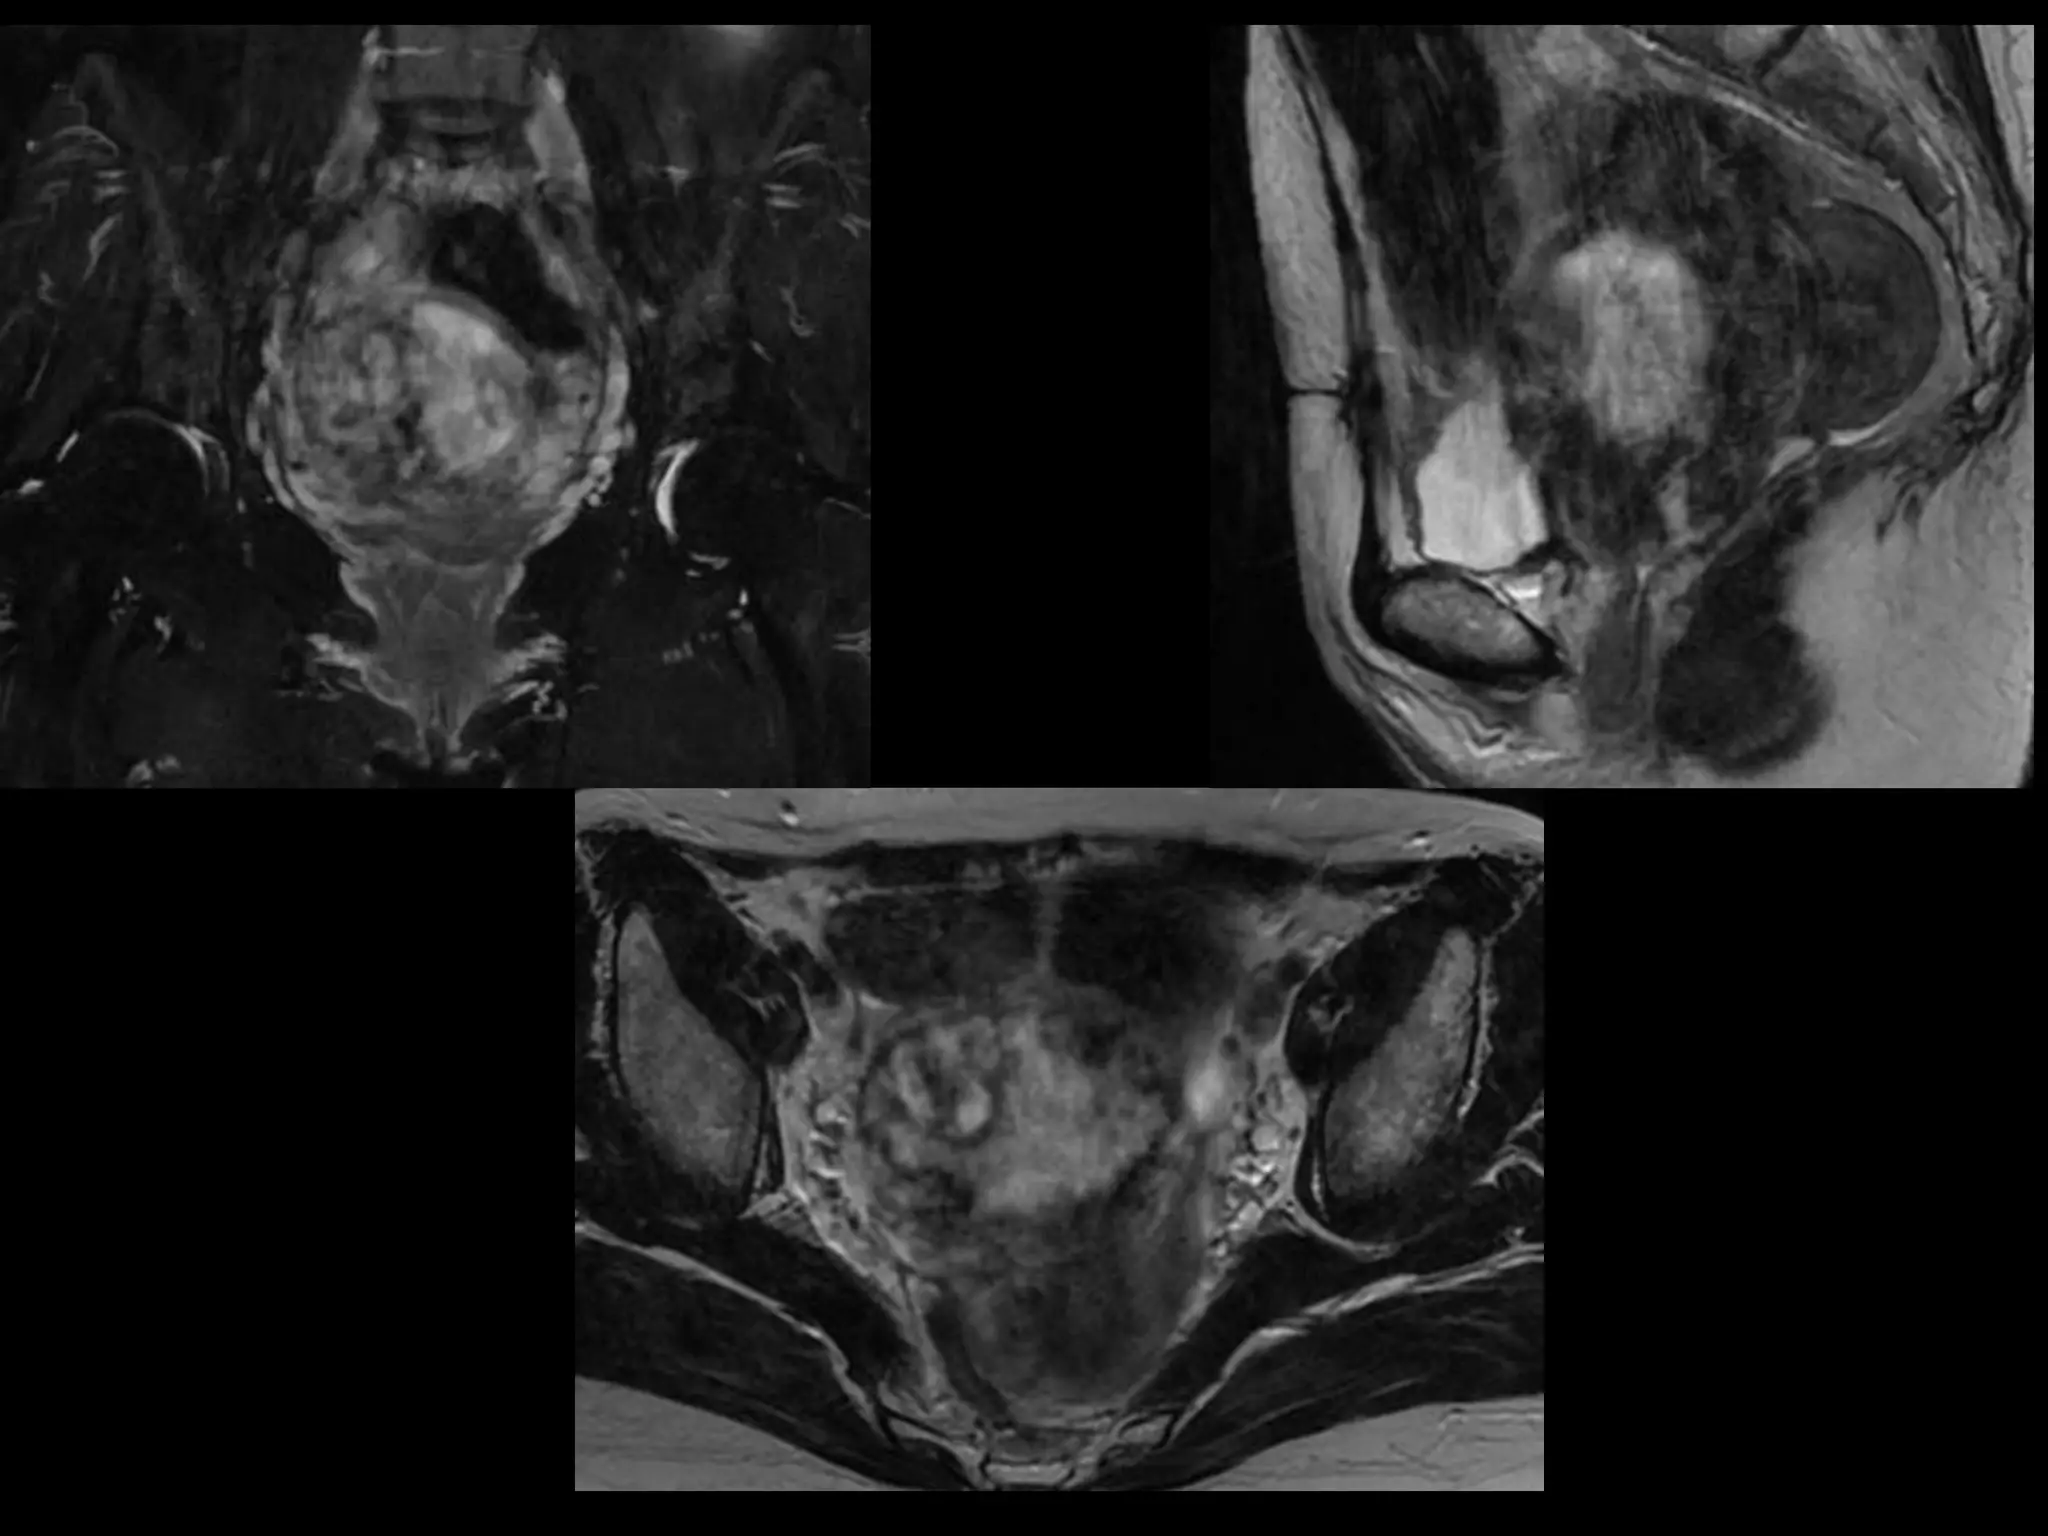

Dr. Hedvig Hricak

HISTORY

โ€ข   42 yo female

โ€ข   Recent immigrant from China

โ€ข   C/O postcoital and intermenstrual bleeding

โ€ข   Abnormal GYN exam

โ€ข   Abnormal biopsy

โ€ข   Further imaging performed

MRI findings - Stage IIB

with PET/CT - Stage IIIB

Cervical Cancer

Stage I โ€“ Carcinoma Confined to Cervix

<= 4 cm greatest dimension   > 4 cm greatest dimension

<= 7 mm wide

A1 < =3mm deep

A2 >3 but < 5mm deep

Stage II โ€“ Carcinoma Invades Beyond Uterus

But not to Pelvic Wall or Lower 1/3 Vagina

With(A) or without (B)

parametrial invasion

Stage III โ€“ Carcinoma to Pelvic Wall and/or Lower 1/3 of

Vagina and/or Causes Hydronephrosis or Nonfxing Kidneys

Lower 1/3 Vagina

No pelvic wall

Extends to pelvic wall

and/or renal issues

Stage IV โ€“ Carcinoma beyond True Pelvis or Involvement

Of Mucosa of Bladder or Rectum (bx proven)

Distant Mets

Spread to adj organs

Role of MR Imaging in Tx Stratification

of GYN (Cervical) Cancer

โ€ข Cervical Cancer โ€“ 2nd most common ca in women

worldwide

โ€“ Developing countries; pk 30-40 yrs

โ€ข FIGO classification โ€“ revised in 2009 from just clinical to

incorporate cross-sectional imaging (CT, MR)

โ€ข Staging accuracy of MR 85-96%

โ€“ Best test to assess tumor size and location; invasion into

parametria, pelvic side wall, adjacent organs; local nodal enlgment

โ€ข PET/CT helpful in staging advanced disease

โ€“ Demonstrates unexpected sites beyond pelvis

โ€ข Treatment options

โ€“ Radical surgery - early stage (IA, IB1, IIA1)

โ€“ Primary Chemo and Radiation โ€“ bulky IB2 or IIA2, or local

advanced (IIB or greater)

Sala et al. Radiology 2013; 266: 717.

HISTORY โ€ข 42 yo female โ€ข Recent immigrant from China โ€ข C/O postcoital and intermenstrual bleeding โ€ข Abnormal GYN exam โ€ข Abnormal biopsy โ€ข Further imaging performed

MRI findings -Stage IIB with PET/CT - Stage IIIB Cervical Cancer

Role of MRImaging in Tx Stratification of GYN (Cervical) Cancer โ€ข Cervical Cancer โ€“ 2nd most common ca in women worldwide โ€“ Developing countries; pk 30-40 yrs โ€ข FIGO classification โ€“ revised in 2009 from just clinical to incorporate cross-sectional imaging (CT, MR) โ€ข Staging accuracy of MR 85-96% โ€“ Best test to assess tumor size and location; invasion into parametria, pelvic side wall, adjacent organs; local nodal enlgment โ€ข PET/CT helpful in staging advanced disease โ€“ Demonstrates unexpected sites beyond pelvis โ€ข Treatment options โ€“ Radical surgery - early stage (IA, IB1, IIA1) โ€“ Primary Chemo and Radiation โ€“ bulky IB2 or IIA2, or local advanced (IIB or greater) Sala et al. Radiology 2013; 266: 717.